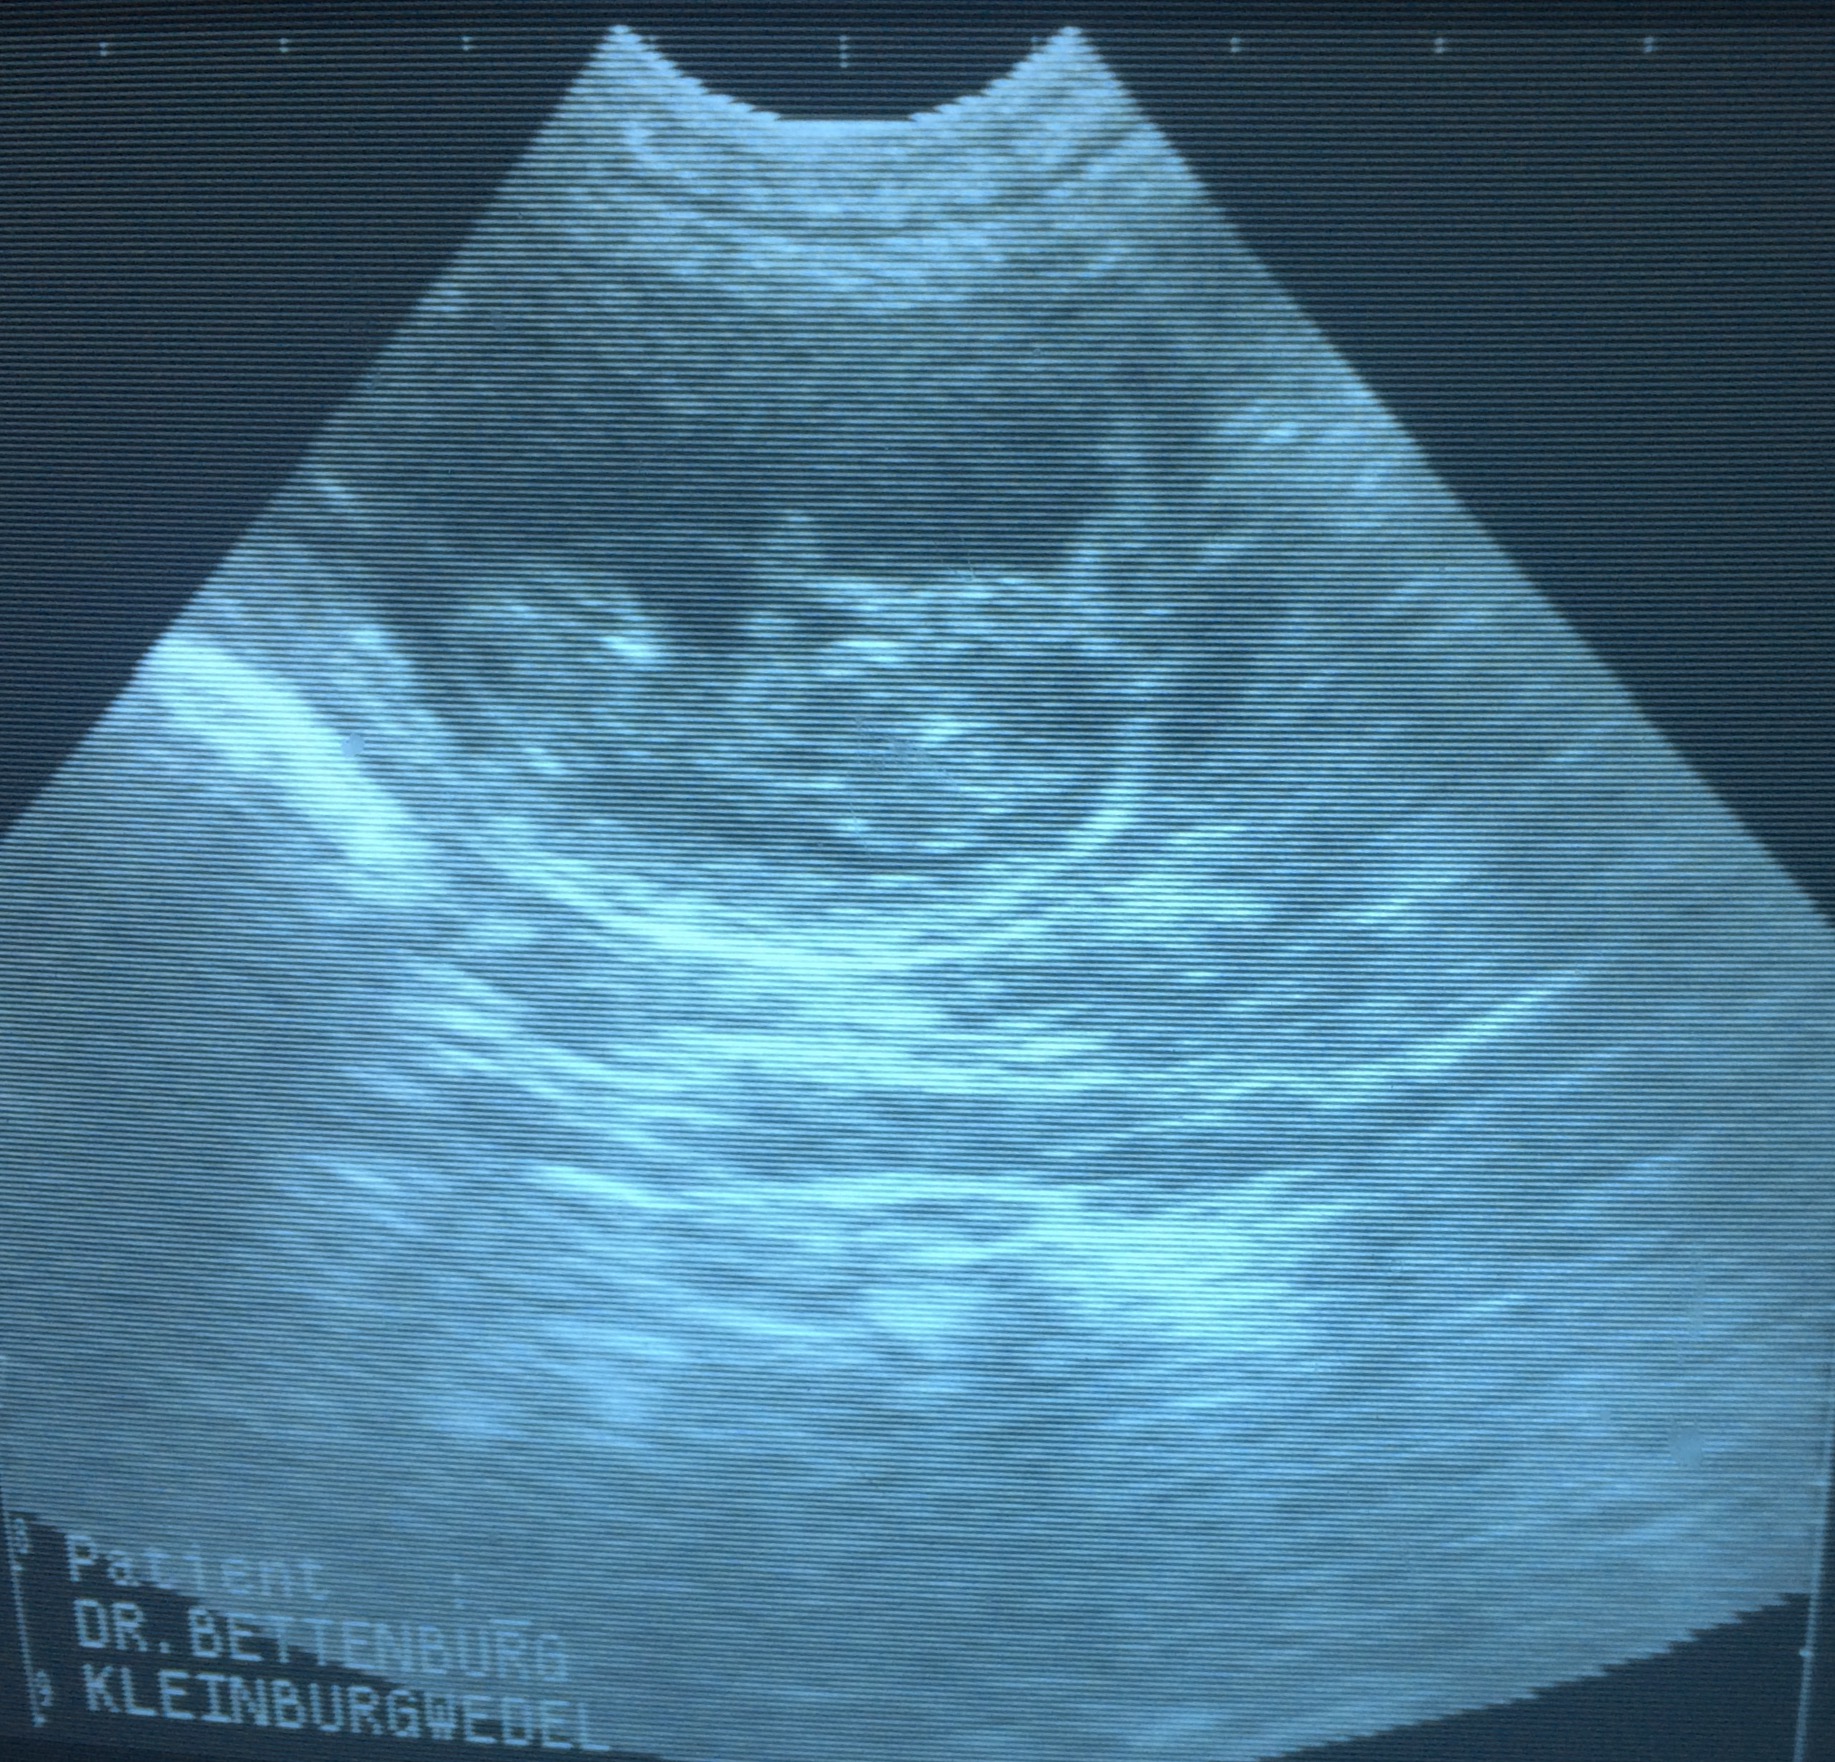

06.11.13 Heute war ich mit Melby beim Ultraschall ;-) und siehe da sie ist trächtig!!! Wir haben viele kleine Baby's gesehen. Ich freu mich riesig auf die schwarzen kleinen Fellnasen.

Jetzt heißt es Daumen drücken und bis zur Geburt warten

Hier die ersten Babyfotos